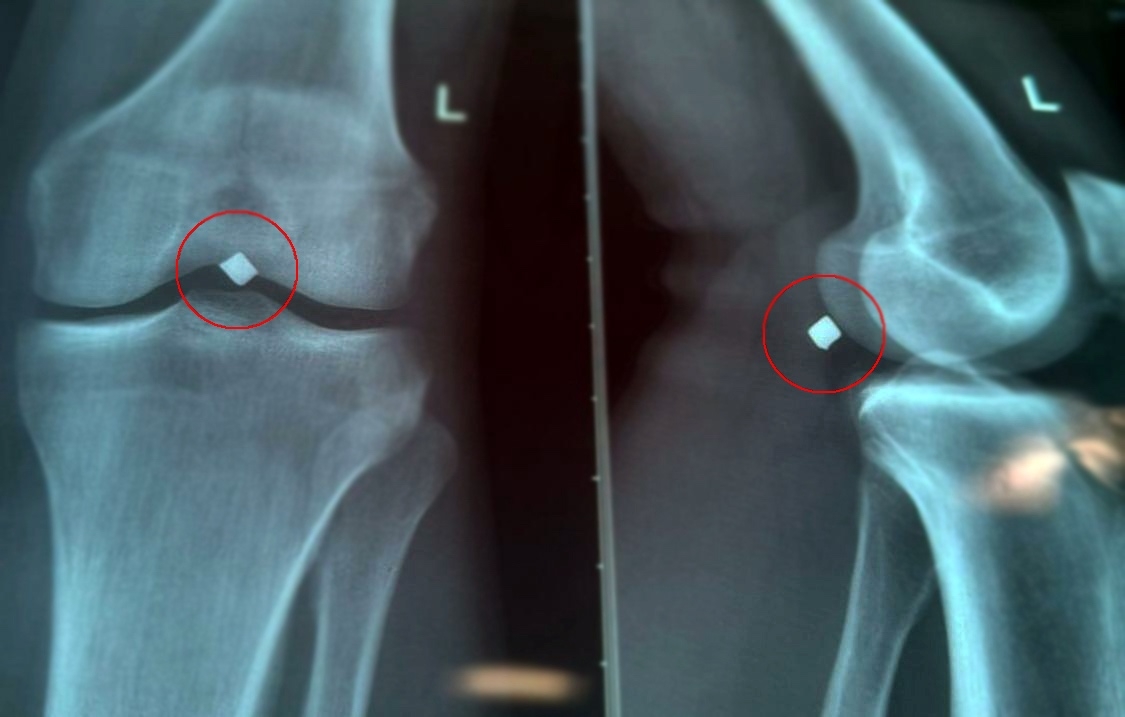

Траектория движения снаряда была впечатляющей: металлический фрагмент проник сквозь надколенник, прошел через полость коленного сустава и остановился буквально в миллиметрах от важного сосудисто-нервного пучка ноги. Из-за постоянного давления на ткани нога постоянно болела, вызывая сильный дискомфорт и ограничивая подвижность.

Обследование показало точное местоположение осколка, и врачи приняли решение провести операцию. Руководивший процедурой кандидат медицинских наук, сердечно-сосудистый хирург Вячеслав Владимирович Карпов, подчеркнул сложность ситуации: металл находился непосредственно рядом с крупной веной, почти касаясь стенки сосуда, что создавало риск серьезного кровотечения.